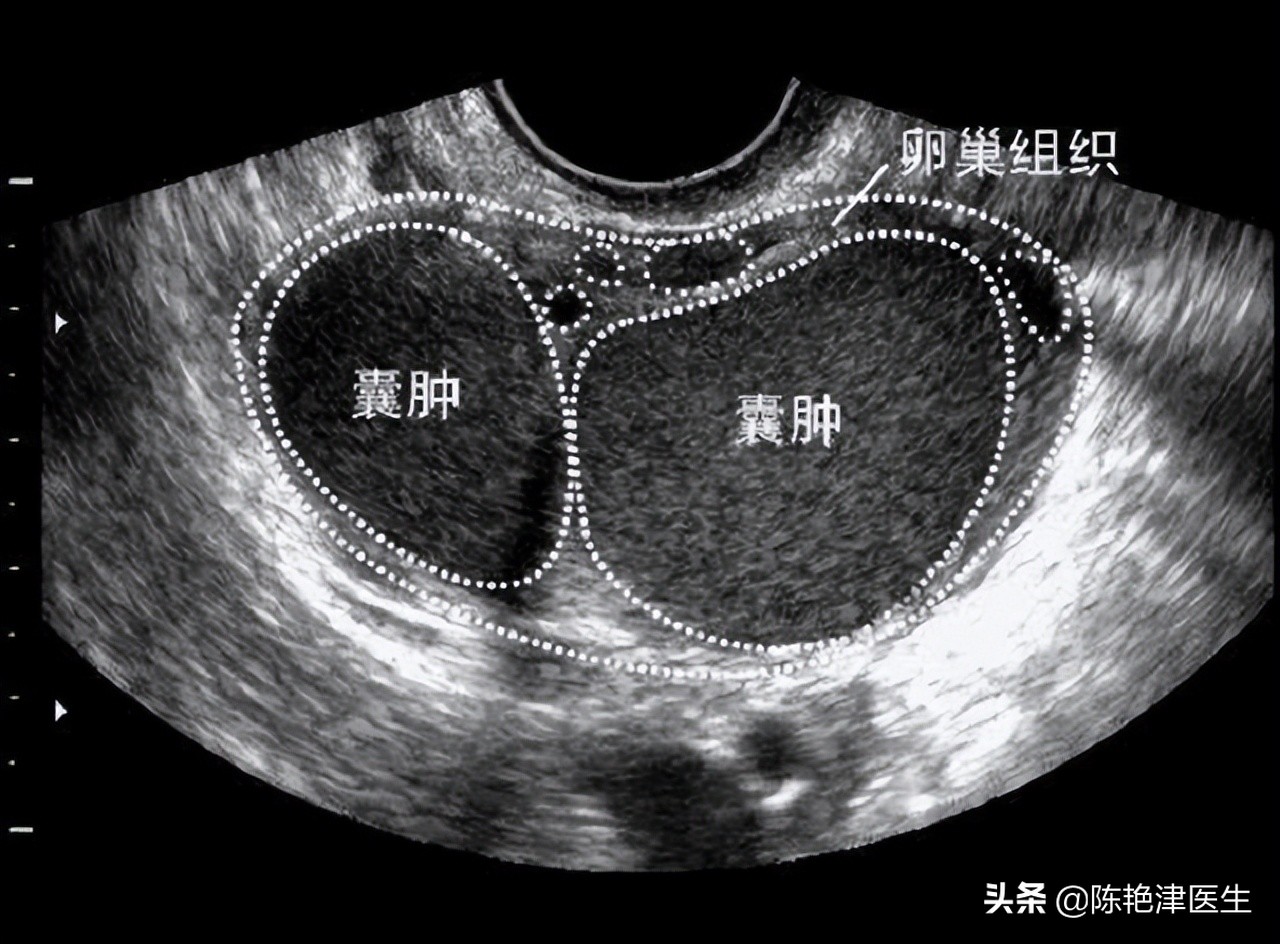

这可吓坏了张女士,而医生紧锁的眉头又紧了几分,因为患者的情况可能比怀上孩子更严重!医生赶紧让张女士带着女儿去做进一步检查,彩超检查发现是 多发囊性肿物,这是女孩肚子中的超大卵巢囊肿!

而且囊肿已经 压迫到肾脏,出现了肾积水,所以女孩的肚子越来越肿,腹痛越来越严重,手术迫在眉睫。